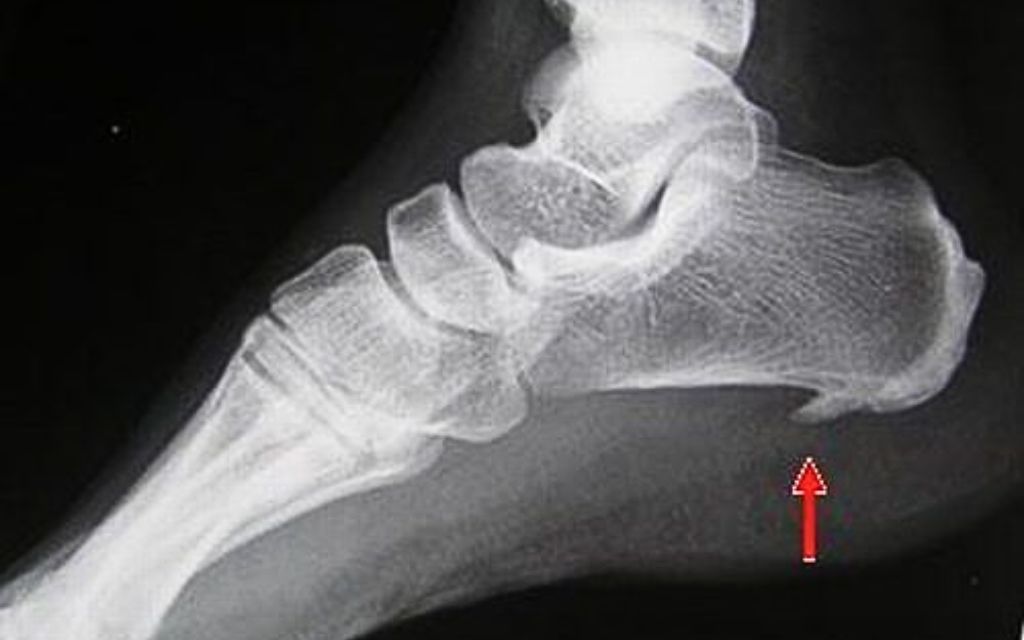

Để chuẩn đoán bệnh chính xác, người bệnh sẽ được kiểm tra và chụp X - quang theo sự chỉ định của bác sĩ điều trị. Nhìn vào phim X - quang dưới đây, bệnh gai xương gót chân là một cái gai xương nhỏ nhô ra đang hướng vào bên trong vòm bàn chân.

Gai xương này sẽ làm ảnh hưởng đến cuộc sống sinh hoạt và việc đi lại của người bệnh khó khăn hơn.